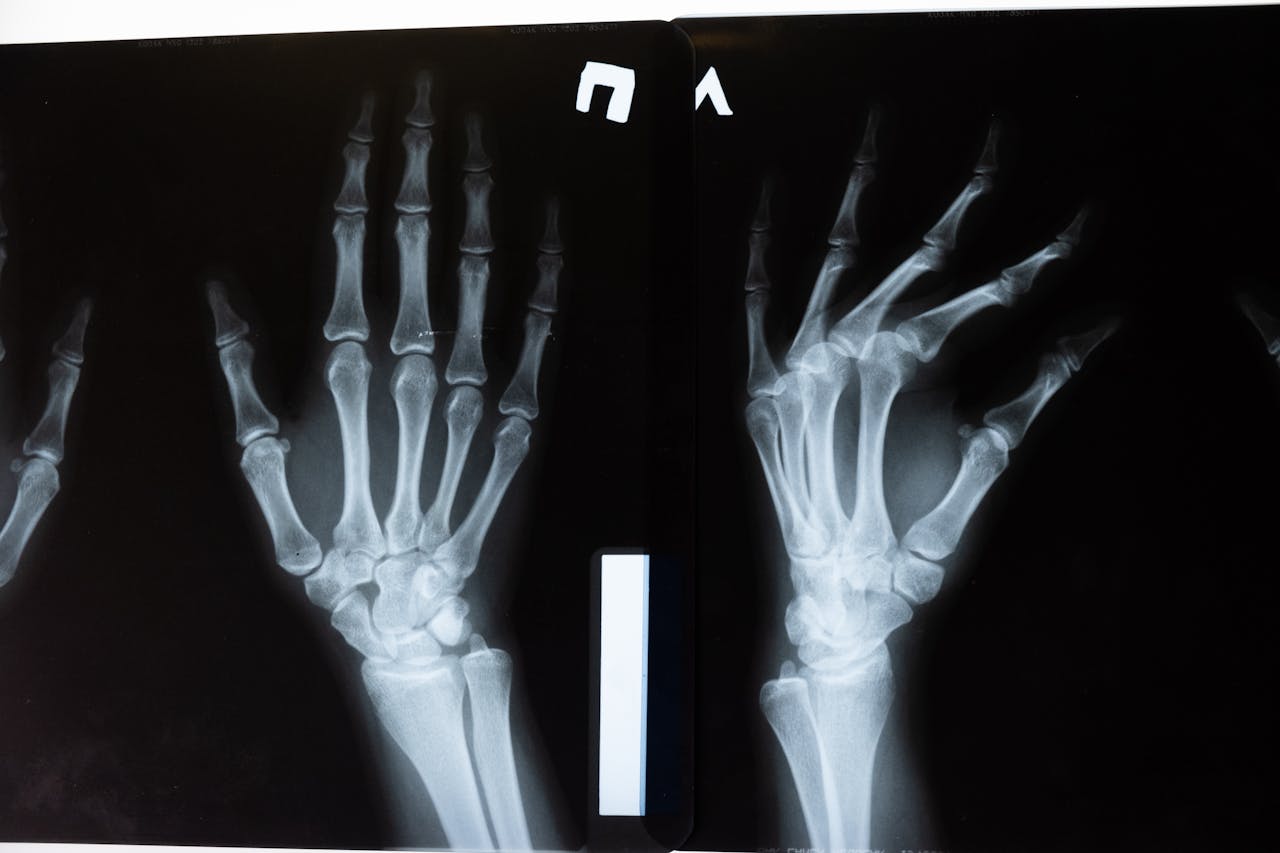

Bone graft

Sumber: https://www.pexels.com/id-id/foto/anatomi-tulang-pemeriksaan-x-ray-5723885/